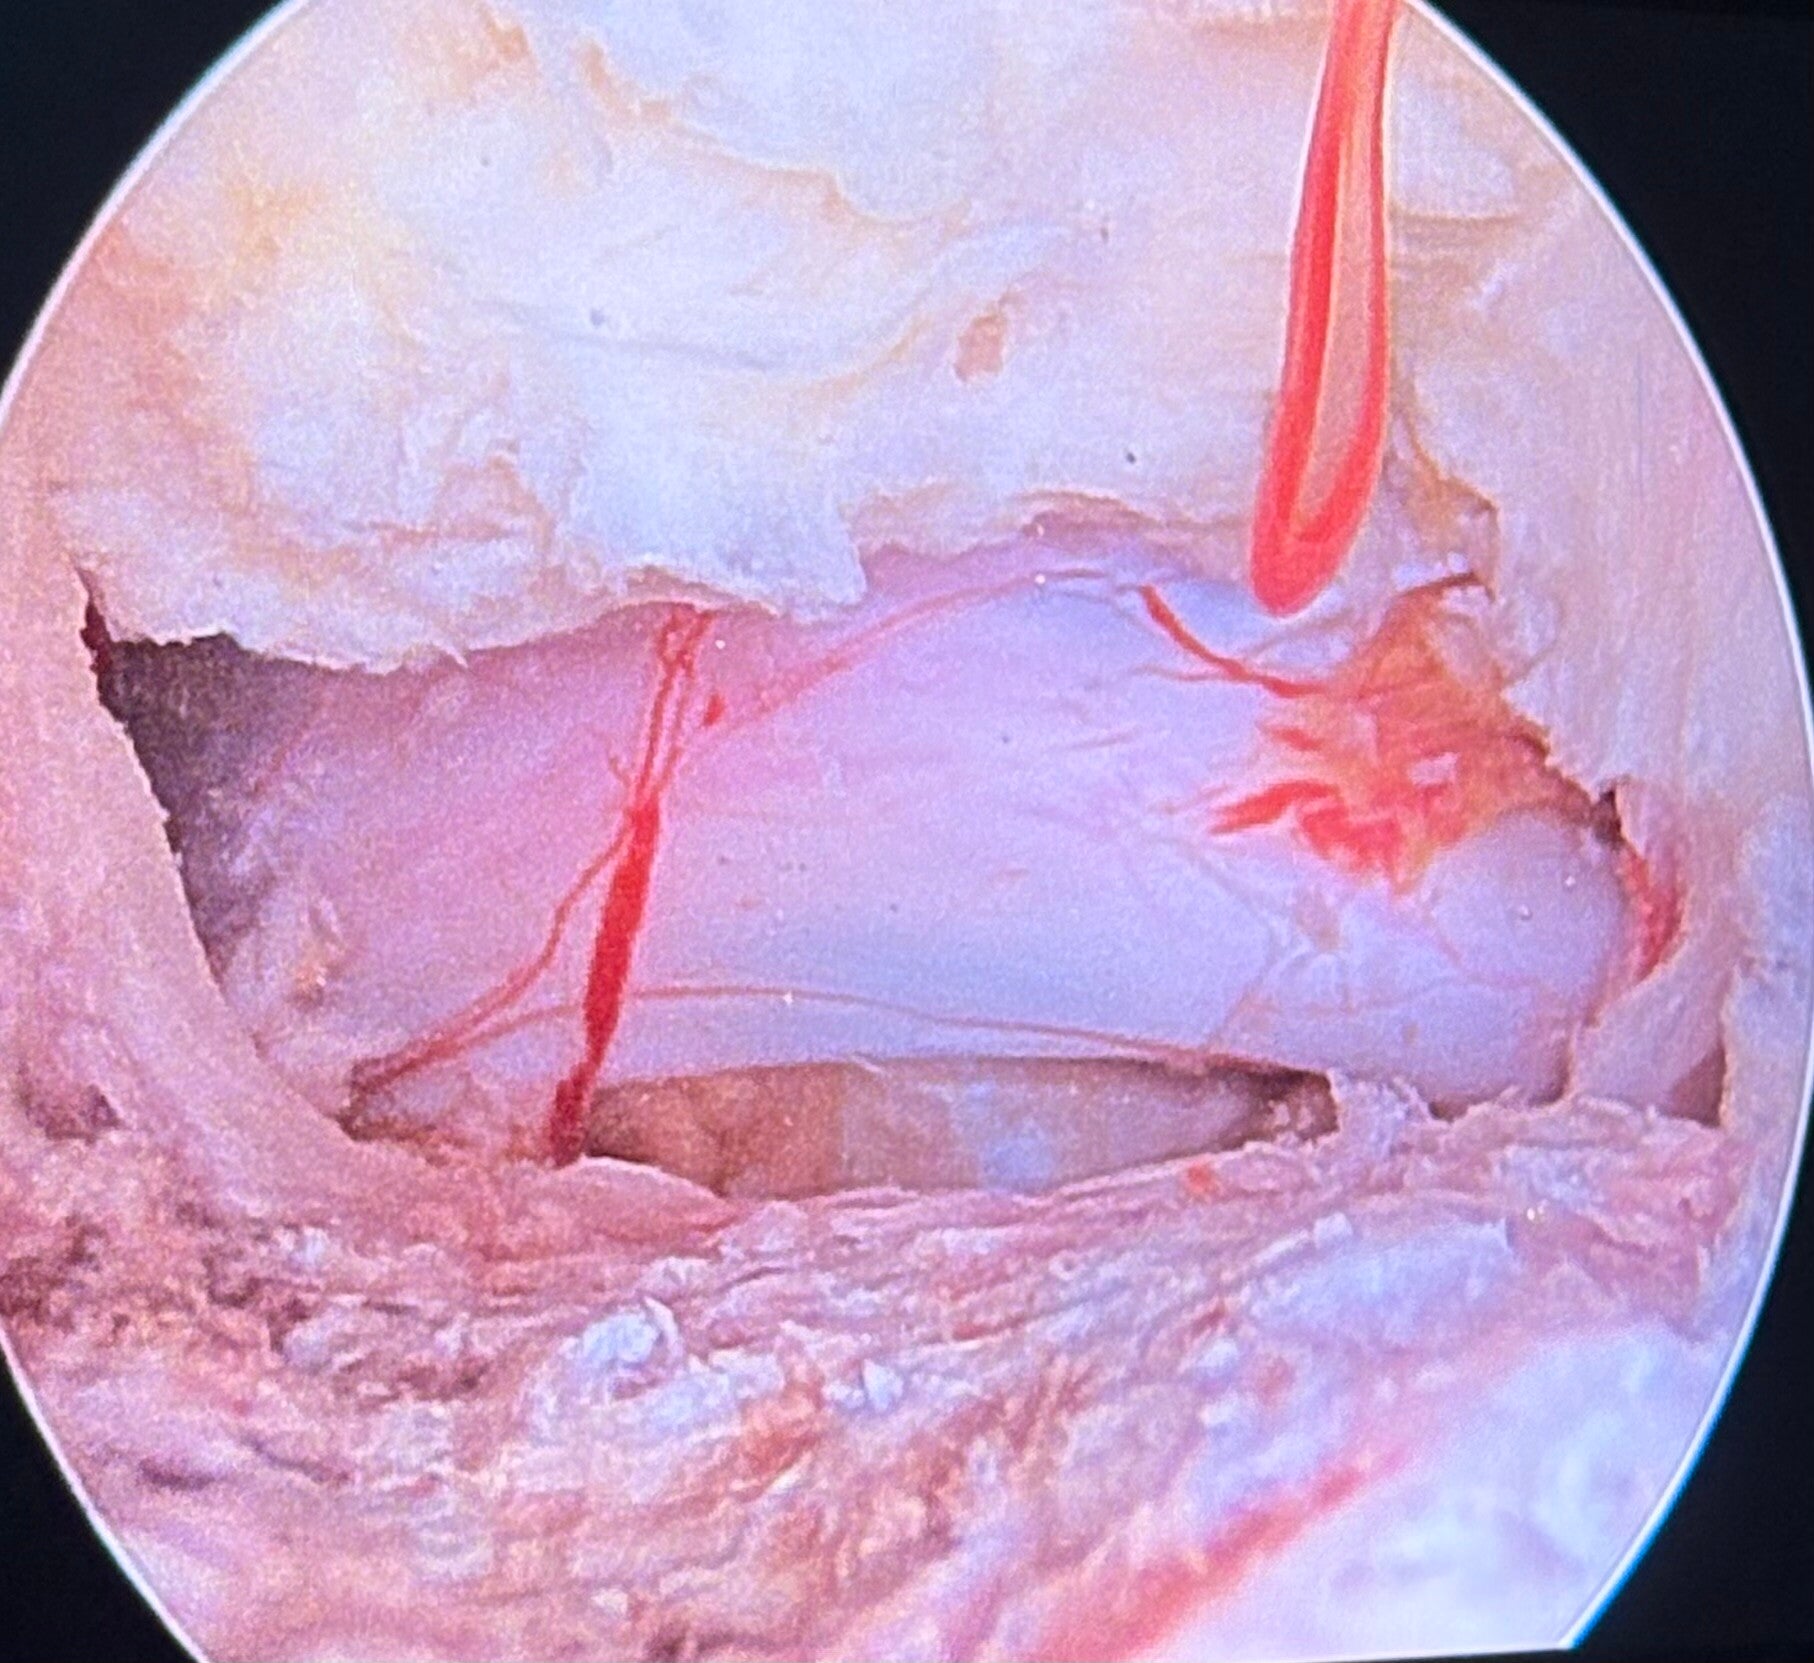

Endoscopie rachidienne - Chirurgie mini-invasive

Selon le type de pathologie, des techniques mini-invasives comme la chirurgie endoscopique biportale (UBE) ou la microchirurgie sous tube et microscope, adaptées au traitement des hernie discales et des canaux lombaires étroits peuvent être utilisés. Ces approches modernes permettent de préserver les muscles, de réduire la douleur postopératoire et de favoriser un retour plus rapide aux activités quotidiennes tout en conservant l'efficacité d’une chirurgie classique.